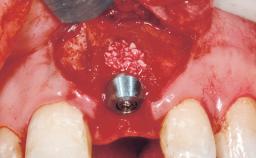

Late Placement of an Implant in a Maxillary Left Central Incisor Site

Type of Implants Two-Piece

Bone Augmentation Horizontal|Staged

Augmentation Materials Xenogenous|Membrane

Bone Volume Deficient horizontally, requiring prior grafting